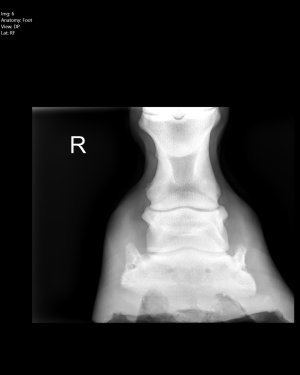

Personally I’d (at least short term) get shoes on him to help address quite clear balance issues. For a variety of reasons, more immediate comfort to assist with better movement (weight loss benefits). Reduce the risk of poor compensatory patterns (potential for soft tissue/arthritic changes).

One alignment is better and you have any weight/metabolic issues under control, by all means aim to remove the shoes.

I’m inclined to agree with ihw re putting shoes on in the short term to correct the imbalances, plus repeat x rays to monitor progress. That is what I did with my homebred with poor front foot balance. The shoes came off again later.

I have to say that I’d not be minded to stay with a farrier who had allowed those imbalances to creep in.